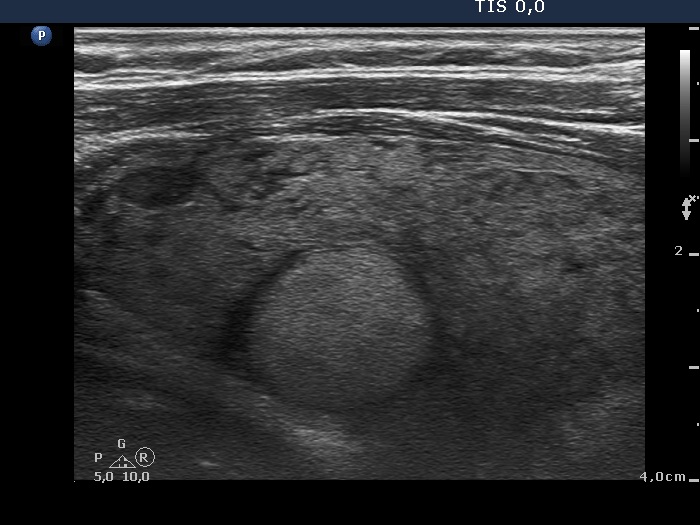

Right lobe, longitudinal scan

Right lobe, longitudinal scan. This is the so-called micronodular form of Hashimoto's thyroiditis.